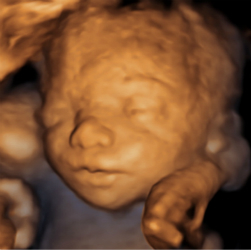

四维超声检查(动态三维超声检查)只是给宝宝拍了一张照片,对胎儿位置和姿势要求较高,胎儿孕周比较大才能拍的好,不能够评价胎儿的结构和发育情况。如果要求了解宝宝的结构是否正常,只需要选择系统产前超声检查。